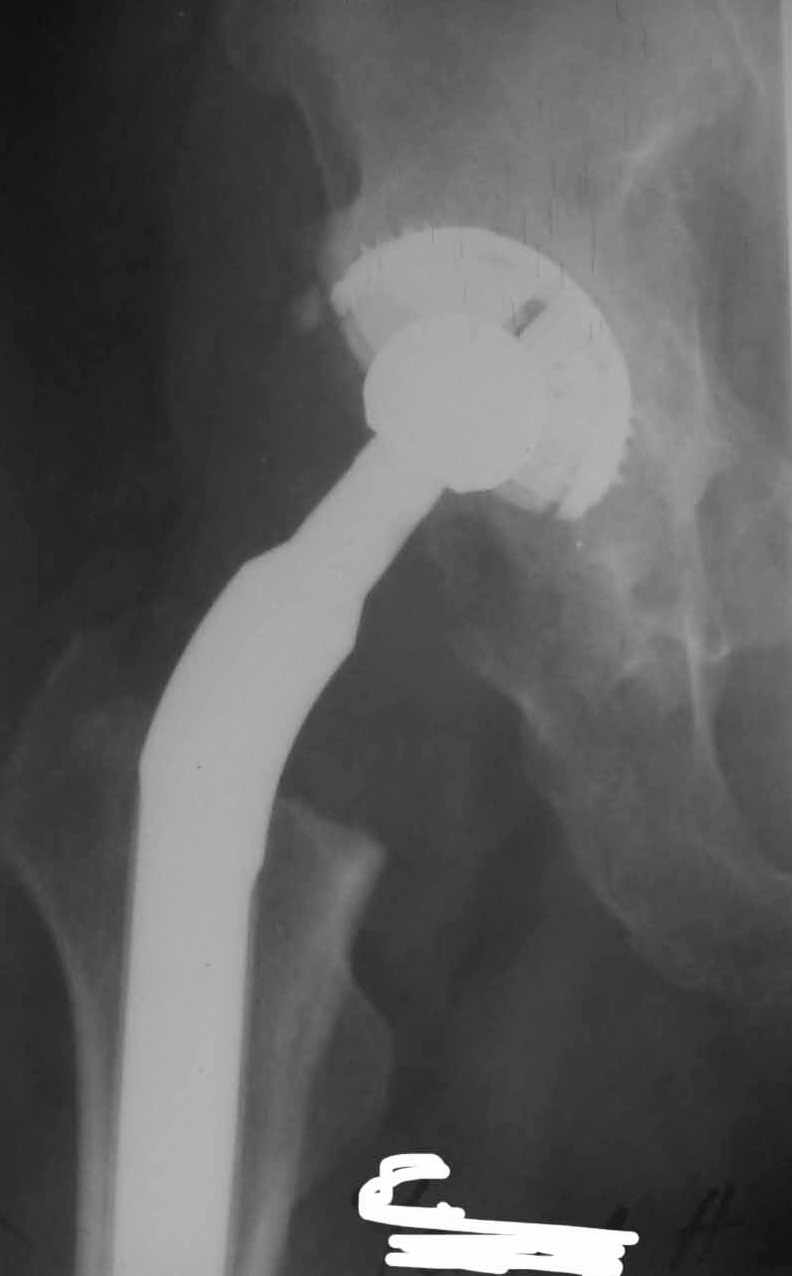

Re: вывих головки эндопротеза

Во вложении - рентгенограммы после вывиха и после вправления.